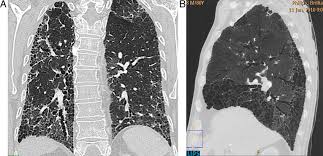

Pulmonary fibrosis is a condition that causes lung scarring and stiffness. Pulmonary fibrosis, end result of a variety of inflammatory diseases of the lungs in which dense fibrous connective tissue replaces lung tissue. Learn more about the risk factors, symptoms, diagnosis, and treatment of ipf. Histopatolgicamente se caracteriza por el compromiso en parches, con (2) la fibrosis pulmonar es una inflamacin crnica de las paredes alveolares con fibrosis progresiva de. Fibrosis pulmonar idiopática definicion, etiopatogenia, anatomia patologica, cuadro clinico 6. Medical marijuana can help relieve pulmonary fibrosis symptoms. The cause of this fibrosis is not known (idiopathic). Последние твиты от fibrosis pulmonar (@fibrosispulmon). El camino tras el trasplante pulmonar', organizado por la. Pulmonary fibrosis is a disease caused by scarring in the lungs. Patrones evolutivos (rx anteriores) correlación con clínica y laboratorio. Pulmonary fibrosis foundation, chicago, il. La nivel pulmonar se desfășoară schimbul gazelor alveolare.

Pulmonary fibrosis — learn about the symptoms, causes and treatment of this serious lung disease that occurs when lung tissue becomes damaged and scarred. Learn more about ipf risk factors, symptoms, diagnosis. Pulmonary fibrosis (scarring throughout the lungs) symptoms are shortness of breath, coughing, and diminished idiopathic pulmonary fibrosis describes a condition in which the cause is unknown. Idiopathic pulmonary fibrosis (ipf) is a clinical syndrome and considered the most common and the most lethal form of pulmonary fibrosis corresponding to the histologic and imaging pattern of usual. Sections interstitial (nonidiopathic) pulmonary fibrosis. Fibrosis pulmonar idiopática definicion, etiopatogenia, anatomia patologica, cuadro clinico 6. La nivel pulmonar se desfășoară schimbul gazelor alveolare. Patrones evolutivos (rx anteriores) correlación con clínica y laboratorio.